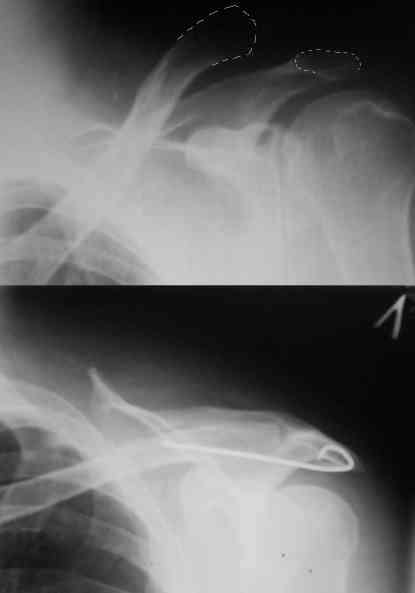

Внешний вид больного (травма: 09.10.2007, операция: 11.10.2007) Ориентиры доступа: овальный – пальпируемый акромиальный конец ключицы, линейный – операционный разрез

Отпрепарированы м\ткани по передней поверхности акромиона Выведен в рану акромиальный конец ключицы

Иссечение разорванного мениска

Подготовка канала в акромиальном конце ключицы сверлом 2,8 мм

Введение крючка в подготовленный канал Дистальная часть крючка подведена под акромион и фиксирована на нем путем загибания (вывих ключицы устранен)

Изготовление крючка из стержня.